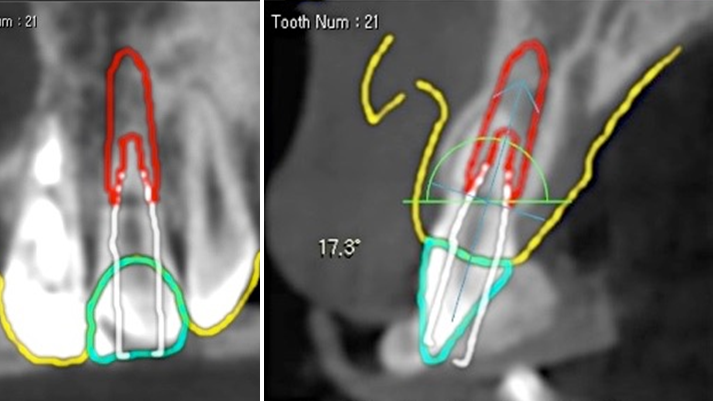

Clinical case: Extraction, immediate placement & loading using

R2GATE solution in aesthetic zone

- Courtesy of Dr. Jong-Cheol Kim, Korea-

Dr. Jong Cheol Kim, immediate loading, digital guided surgery, Digital ONE-DAY Implant, maxillary anterior, #21, guided surgery, immediate loading, AnyRidge, R2GATE, Mega ISQ, MEG Torq, R2GATE Full Surgical Kit

AnyRidge implant system, R2 Guide, R2GATE Full Surgical Kit, Mega ISQ